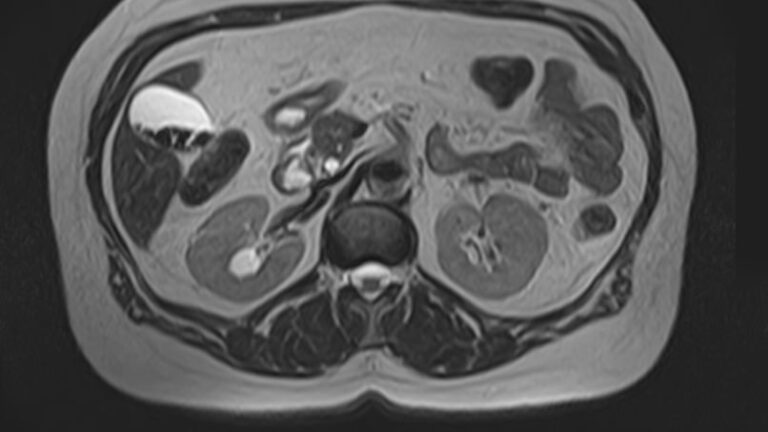

Мочеточники — это парные трубчатые органы, длиной приблизительно 25-30 см, соединяющие почечные лоханки с мочевым пузырем. Наиболее частой патологией является нарушение оттока мочи по мочеточнику за счет сужения (стриктуры) или обтурации (полной закупорки) его просвета.

Магнитно-резонансная томография позволяет получить информацию о состоянии мочеточников и окружающих мягких тканей для точной диагностики заболеваний данной анатомической области.

В первую очередь необходимо отметить, что магнитно-резонансная томография мочеточников выполняется в комплексном обследовании почек и мочевыводящих путей, как самостоятельный метод диагностирования невозможен.

При помощи магнитно-резонансной томографии удается оценить состояние органов и выявить имеющиеся патологии:

- оценить топографическое положение и выявить аномалии развития данного органа;

- оценка кровоснажения мочеточников;

- выявить патологические очаги и имеющиеся зоны поражения в мочеточниках;

- определить наличие новообразований, его размеры;

- оценить функциональность данного органа.